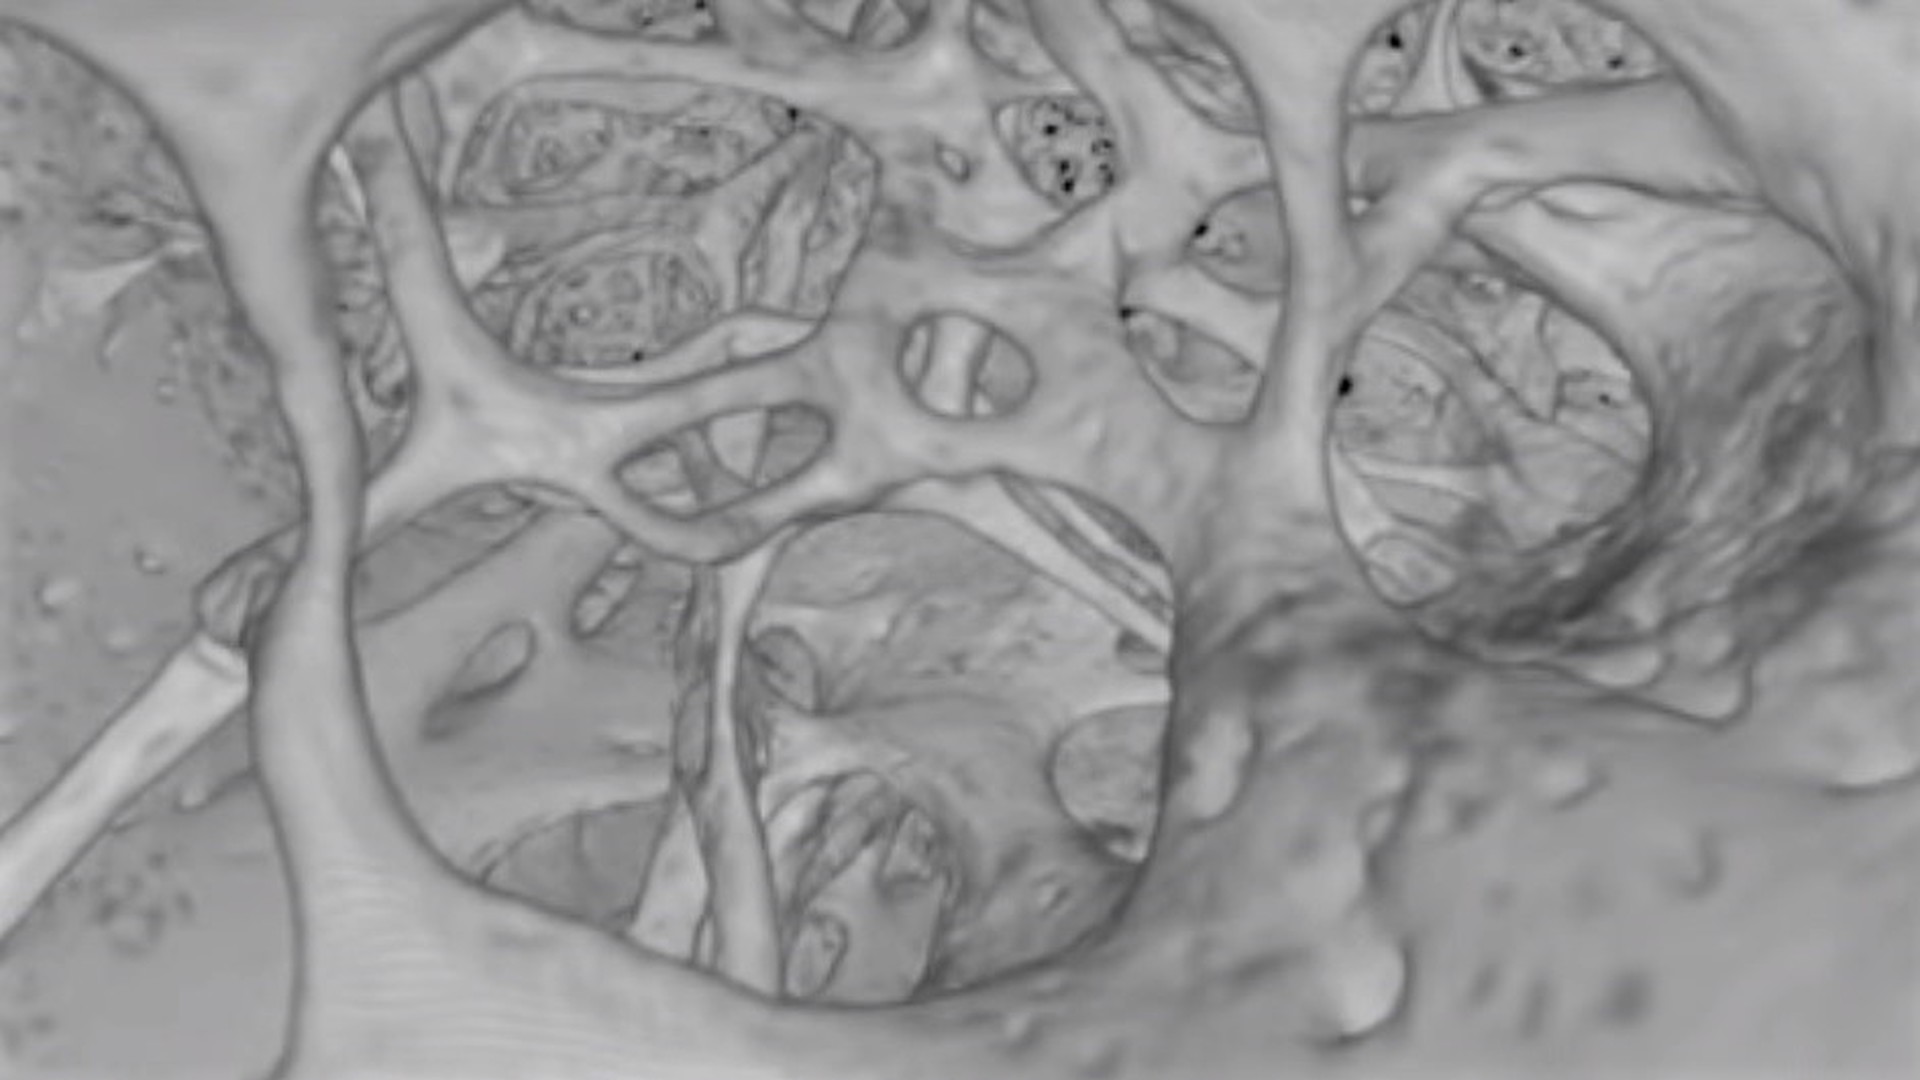

Международная команда учёных сообщила об открытии, которое перепишет учебники по анатомии. В костях человека найдены кровеносные сосуды совершенно нового для науки типа.

По словам исследователей, обнаруженные сети мелких сосудов, похожие на крошечные тоннели, проходят от поверхности костей в их внутренние полости. Судя по всему, благодаря им кровь и иммунные клетки, вырабатываемые в костном мозге, могут быстро и эффективно распространяться по всему телу.

Затем специалисты применили комбинацию нескольких методик, в том числе световой флуоресцентной микроскопии и рентгеновской микроскопии. Они заметили внутри костей, составляющих голень мыши, несколько сотен крошечных кровеносных сосудов, проходящих через кортикальный (твёрдый внешний) слой.

Обнаруженные сосуды были названы транскортикальными.

Оказалось, что мышиная большеберцовая кость, которая по размерам меньше спички, может содержать более тысячи таких маленьких сосудов. Что удивительно, через их сеть проходит более 80% артериальной крови и около 59% венозной крови.

На следующем этапе команда решила проверить наличие транскортикальных сосудов в костях человека. "Подопытным" выступил сам Маттиас Гунцер. В результате оказалось, что кости людей также пронизаны сетью из сосудов нового типа. Конечно, у человека они более широкие по сравнению с мышиными.